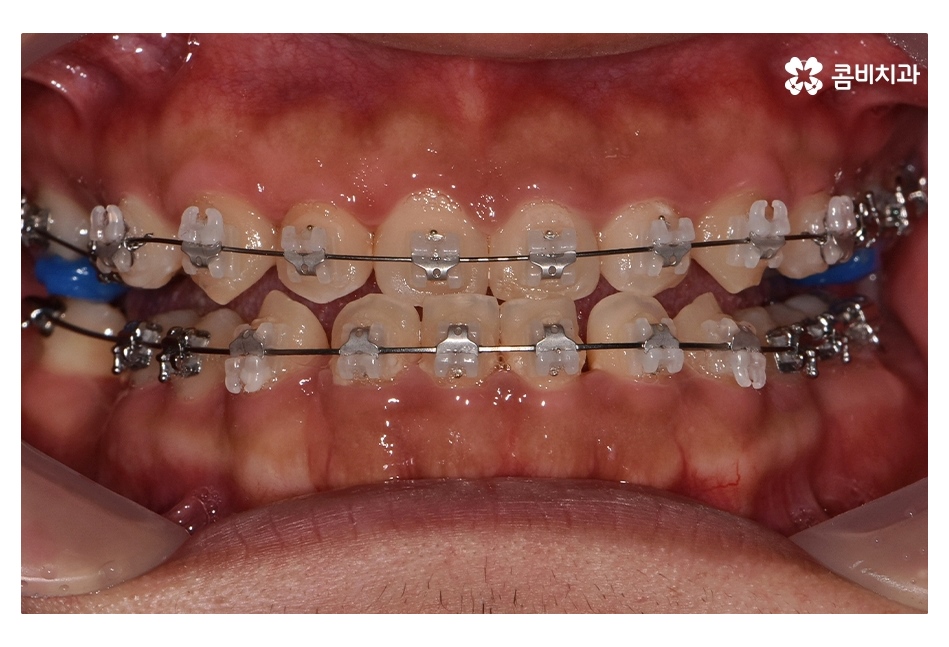

클리피씨교정을 통해서 약 1년 6개월간

치료가 진행이 되었고, 수술과 병행이되며, 치료 마무리 단계에서

임플란트 수술까지 진행이 된 사례라고 볼 수 있는데요.

클리피씨교정은 자가결찰 방식으로 와이어를 고정하고 있으며

일반교정과는 다르게 치아를 이동시킬 때 마찰을

줄일 수 있기 때문에 치아의 이동 속도가 빨라지며

클리피씨교정이 진행되고 시간이 지날수록 아랫니가

점점 윗니에 덮이는 정상 교합의 상태로 개선되는 것을 볼 수 있는데요.